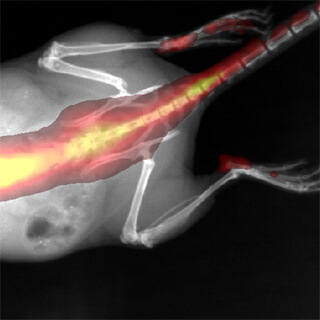

Aparat do przyżyciowego obrazowania zwierząt laboratoryjnych IVIS Lumina XRMS przeznaczony jest do badań dwuwymiarowych z zastosowaniem obrazowania luminescencyjnego, fluorescencyjnego oraz obrazowania promieniowania Cerenkova, a także RTG. Umożliwia to uzyskiwanie złożonych obrazów sygnałów fluorescencyjnych lub /i luminescencyjnych w kontekście obrazu RTG budowy anatomiczne zwierzęcia. Zaawansowana optyka, duży wybór filtrów wzbudzeniowych i emisyjnych, technologia Spectral Unmixing oraz wyposażenie dodatkowe takie jak dedykowany system anestezji gwarantują szerokie spektrum zastosowań aparatów IVIS Lumina XMRS zarówno w badaniach nad nowymi lekami, komórkami macierzystymi, rozwojem stanu zapalnego jak i w badaniach nad terapiami spersonalizowanymi. Standaryzacje badań gwarantuje możliwość absolutnej kalibracji zgodnej ze standardami NIST.

Wysoka czułość obrazowania w zakresie luminescencji oraz promieniowanie Cerenkova

Obrazowanie fluorescencyjne do bliskiej podczerwieni

- Możliwość składania obrazów z fluorescencyjnych, luminescencyjnych i RTG.

Obrazowanie fluorescencyjne do bliskiej podczerwieni